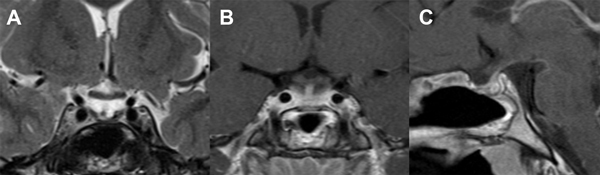

A los 3 meses de la cirugía se realizó una IRM que evidenció una hipófisis conservada, sin alteraciones ni realces patológicos, con quiasma óptico libre y bien posicionado (Fig. 3).

Figura 3. A: IRM T2 coronal. Se visualiza cisterna supraselar libre. B y C: IRM T1 coronal y sagital con gadolinio que muestran hipófisis conservada con captación normal del tallo y glándula.